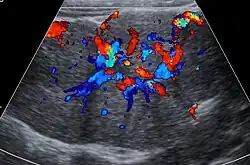

Unenhanced CT or MRI usually does not show the difference in intensity between the focal nodular hyperplasia and surrounding liver except when there is marked liver steatosis that reduces the attenuation of the liver, causing focal nodular hyperplasia to be hyperattenuating when compared with the surrounding liver. In the arterial phase CT or MRI, there is a strong enhancement not followed by washout. The lesion presents a slight hyperintensity or isodensity on portal venous phase or delayed phase images. There is also a presence of a central scar and absence of a capsule for the focal nodular hyperplasia.[7]